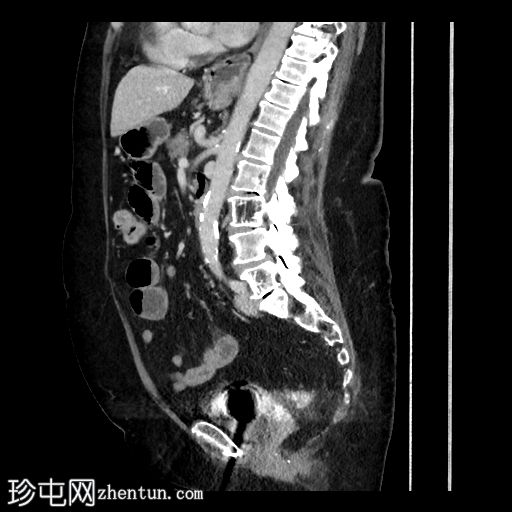

矢状位增强扫描(门静脉期)

可见小食管裂孔疝。胆道积气。胆囊增厚,相对减压,并伴有胆囊十二指肠瘘。空肠至回肠近端中度扩张,回肠近端可见节段性增厚,并延伸至右下腹的移行点。移行点处可见一枚卵圆形层状胆结石,周围有少量吞咽物。双侧全髋关节置换术导致盆腔出现条状伪影。未见其他急性异常。

这是一个典型的胆石性肠梗阻病例,伴有胆囊十二指肠瘘,移行点位于右下腹近端回肠(里格勒三联征)。请注意,肠壁在移行点附近轻度增厚,阻塞性胆结石可能与吞咽物混杂在一起,容易被忽略。此外,还应注意胆囊肠瘘可能被误认为是正常的上消化道解剖结构或十二指肠憩室。这些观察结果有助于强调全面检查的重要性。